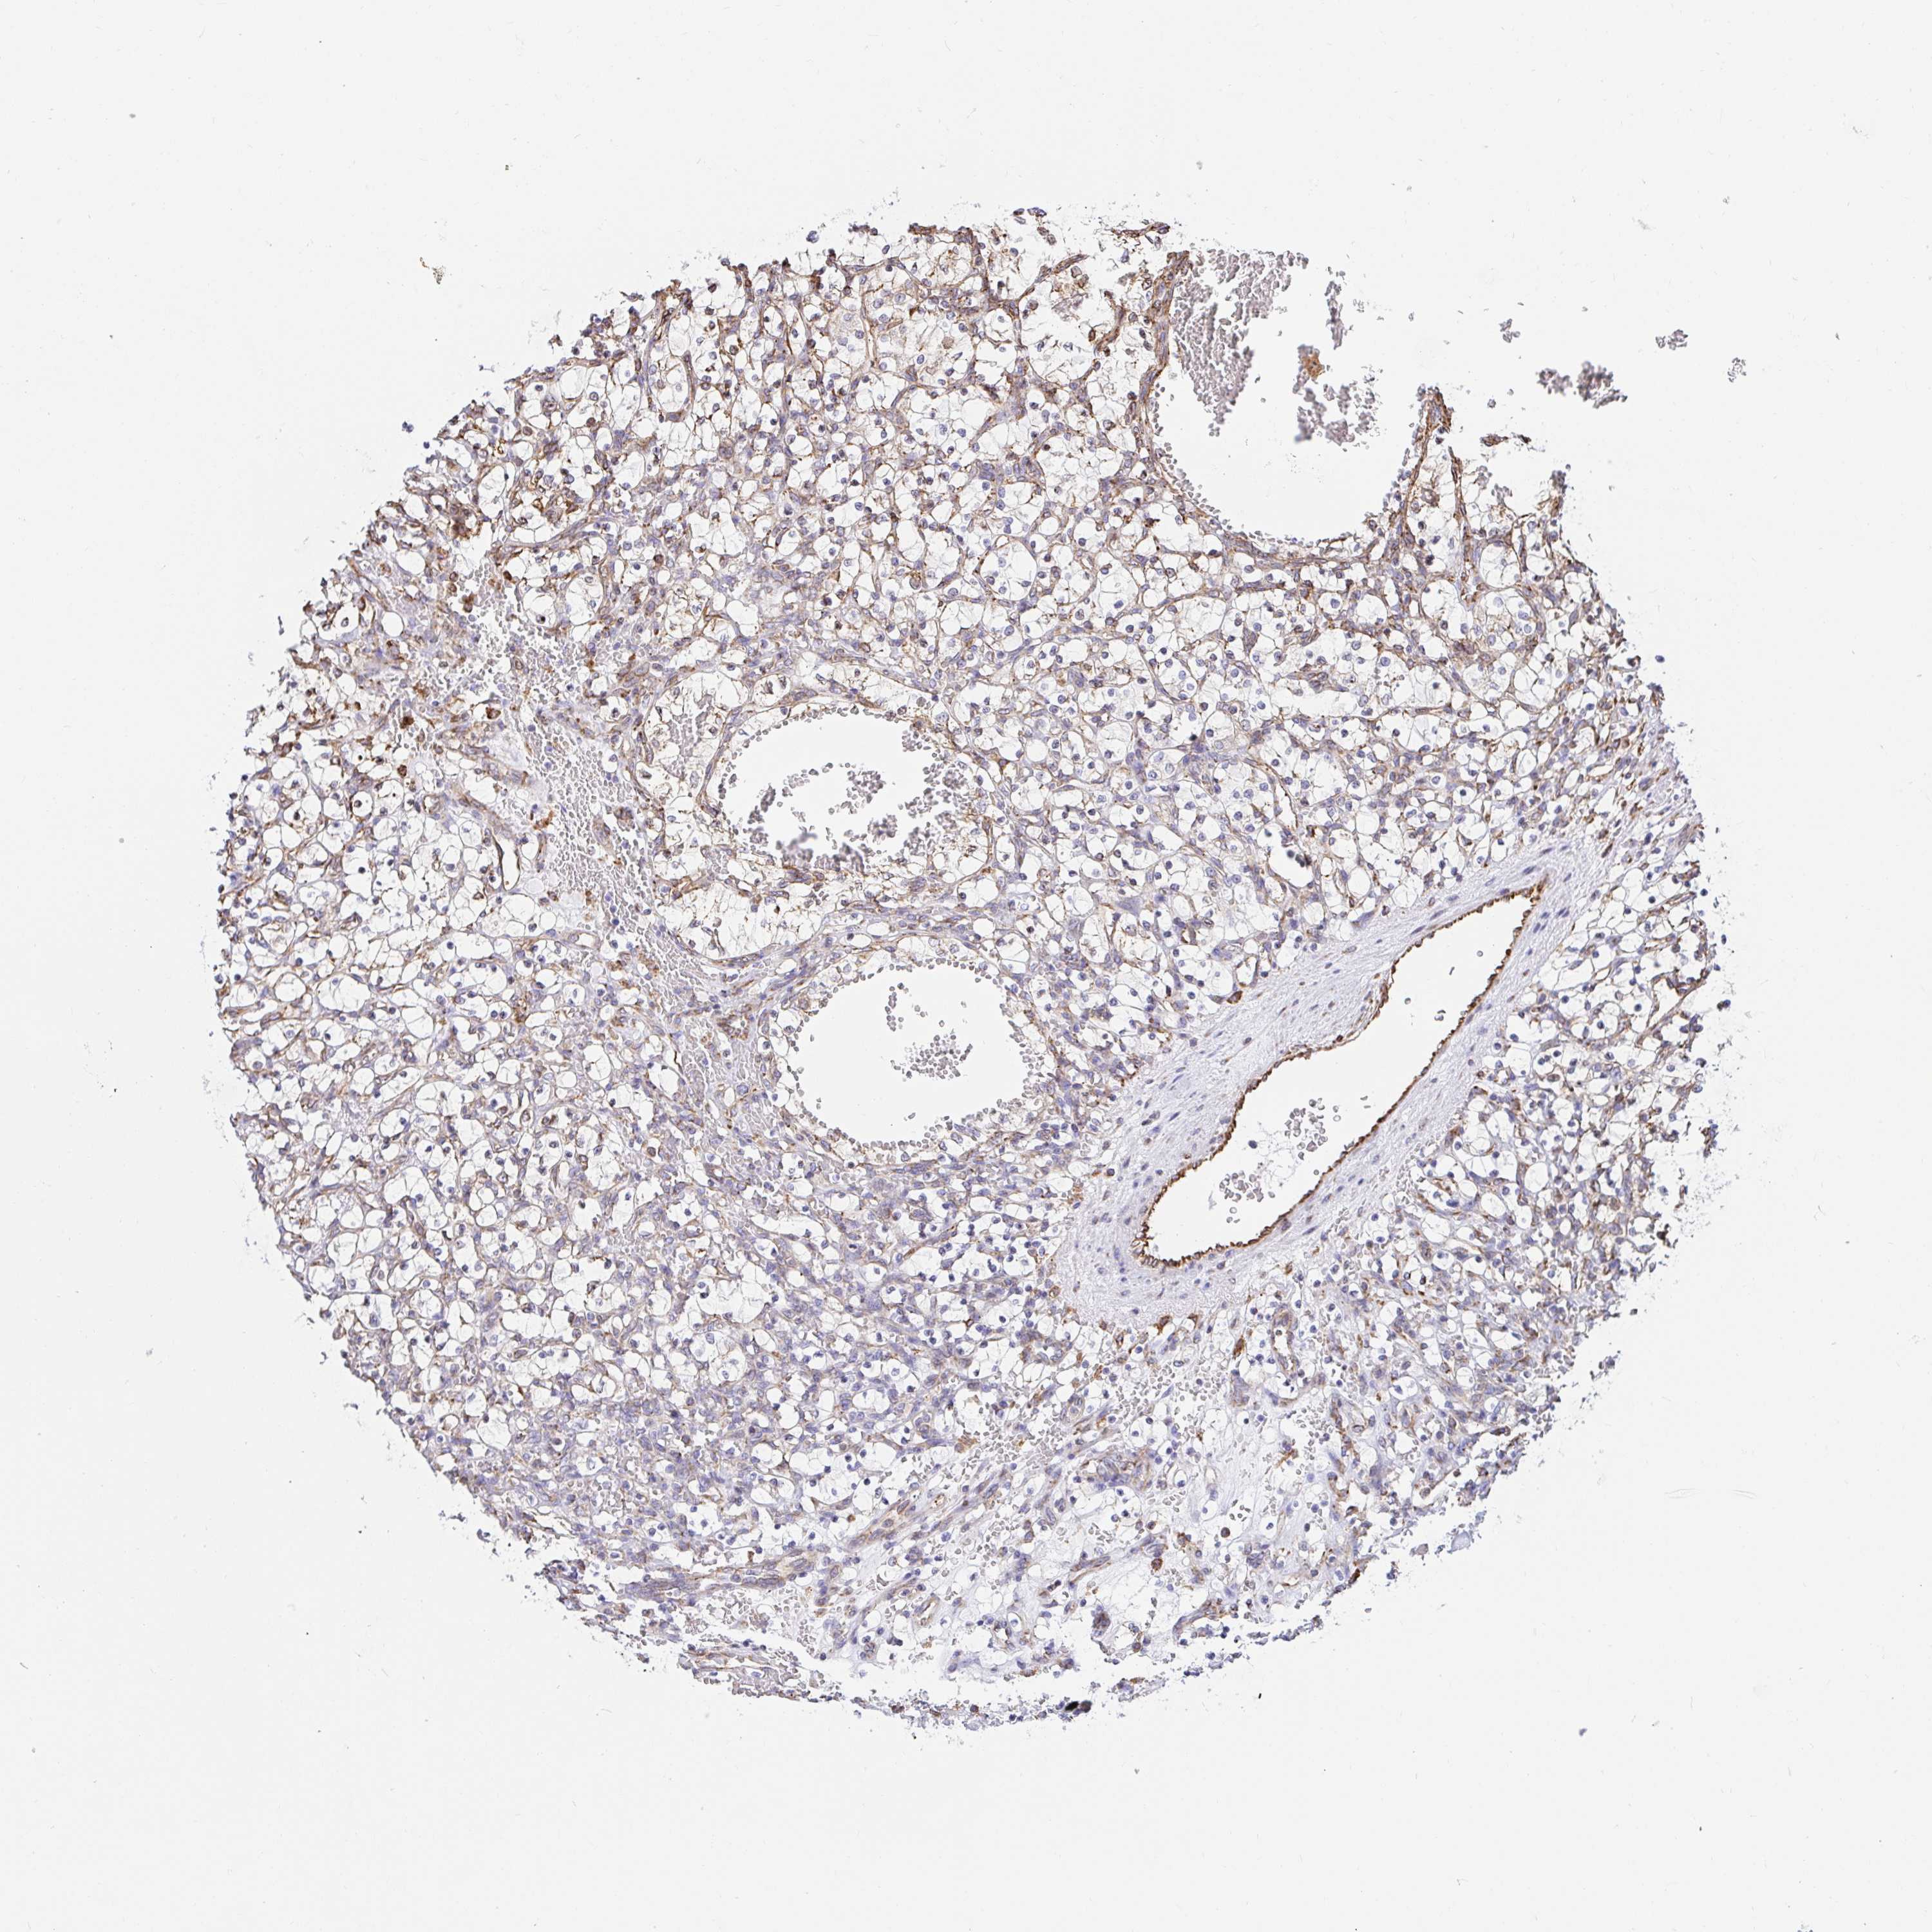

KIDNEY RENAL CLEAR CELL CARCINOMA (VALIDATION) - Interactive survival scatter ploti

The Survival Scatter plot shows the clinical status (i.e. dead or alive) for all individuals in the patient cohort, based on the same data that underlies the corresponding Kaplan-Meier plots. Patients that are alive at last time for follow-up are shown in blue and patients who have died during the study are shown in red.

The x-axis shows the expression levels (FPKM) of the investigated gene in the tumor tissue at the time of diagnosis. The y-axis shows the follow-up time after diagnosis (years). Both axes are complimented with kernel density curves demonstrating the data density over the axes. The top density plot shows the expression levels (FPKM) distribution among dead (red) and alive patients (blue). The right density plot shows the data density of the survived years of dead patients with high and low expression levels respectively, stratified using the cutoff indicated by the vertical dashed line through the Survival Scatter plot. This cutoff is automatically defined based on the FPKM cutoff that minimizes the p-score. The cutoff can be changed by dragging the vertical line or by entering a cutoff value in the square labeled "Current cut-off".

Under the Survival Scatter plot the p-score landscape (black curve; left axis) is shown together with dead median separation (red curve; right axis). Dead median separation is the difference in median mRNA expression between patients who have died with high and low expression, respectively. It is calculated as follows: median FPKM expression of dead patients with high expression - median FPKM expression of dead patients with low expression. This is intended to aid the user in visually exploring custom cutoffs and the associated p-scores and dead median separation.

Individual patient data is displayed and can be filtered by clicking on one or more of the category buttons on the top of the page. Categories describing expression level and patient information include: high, low, alive, dead, female, male and tumor stages. The scale of the x-axis can be toggled between linear and log-scale by clicking on the "x log" button. Mouse-over function shows TCGA ID, patient information and mRNA expression (FPKM) for each patient.

& Survival analysisi

Kaplan-Meier plots summarize results from analysis of correlation between mRNA expression level and patient survival. Patients were divided based on level of expression into one of the two groups "low" (under cut off) or "high" (over cut off). X-axis shows time for survival (years) and y-axis shows the probability of survival, where 1.0 corresponds to 100 percent.

CLGN is not prognostic in Kidney Renal Clear Cell Carcinoma (validation)

Best expression cut offi

Based on the FPKM value of each gene, patients were classified into two groups and association between prognosis (survival) and gene expression (FPKM) was examined. The best expression cut-off refers the FPKM value that yields maximal difference with regard to survival between the two groups at the lowest log-rank P-value. Best expression cut-off was selected based on survival analysis .

When clicking on this number, the vertical dashed line indicating cut-off, the interactive survival plot, and the Kaplan-Meier curve will be adjusted to show results based on the best expression cut-off.

: 0.53

Average pTPM 2.6

Number of samples 100